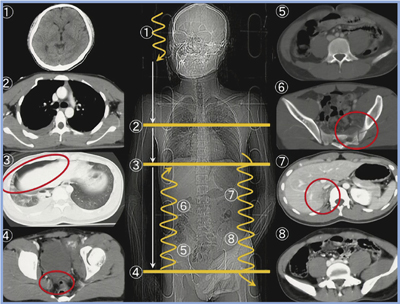

現在,われわれは外傷CTについて,出来上がってくる画像をその場で順番に観察し,3分以内で全身を評価する“FACT(Focused Assessment with CT for Trauma)”という読影方法を推奨している。この方法は,外傷初期診療ガイドラインにおいても,標準的な読影方法に置き換わってきている。FACTでは図9のように,頭部(血腫の有無等)⇒大動脈損傷の有無⇒気胸・血胸の有無⇒腹腔内血腫の有無⇒骨盤・椎体骨折の有無⇒腹部臓器,という順番で3分以内に読影を行う。

FACTを撮影を行っている間に実施するためには,短時間での撮影・画像提供が必要となる。すなわち,Aquilion PRIMEのような短時間撮影・短時間再構成が可能なCTでないと実現できないということになる。

図9 外傷CTの読影方法“FACT”